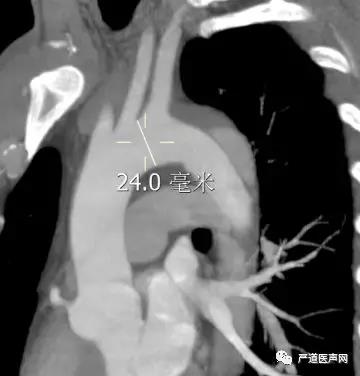

辅助检查:CTA示主动脉穿透性溃疡(Stanford B型,Debakey III型),参考直径24mm。